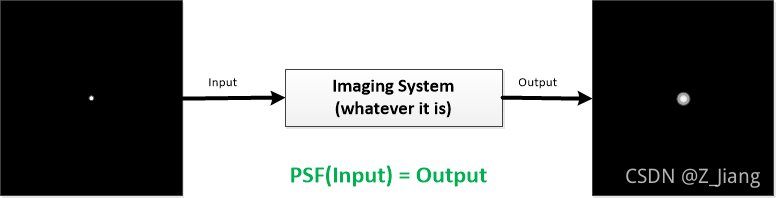

Apodization实际是以Main Lobe稍微变宽为代价,换来一级旁瓣大幅压制,but anyway还是一笔划算的compromise。上面以理想靶点为输入,得到的图像,我们常称为PSF(Point Spread Function)。PSF是泛指任意成像系统,当输入为一个delta function时,它的输出结果成像所对应的抽象函数,它描述了成像系统本身,如下图所示

PSF示意